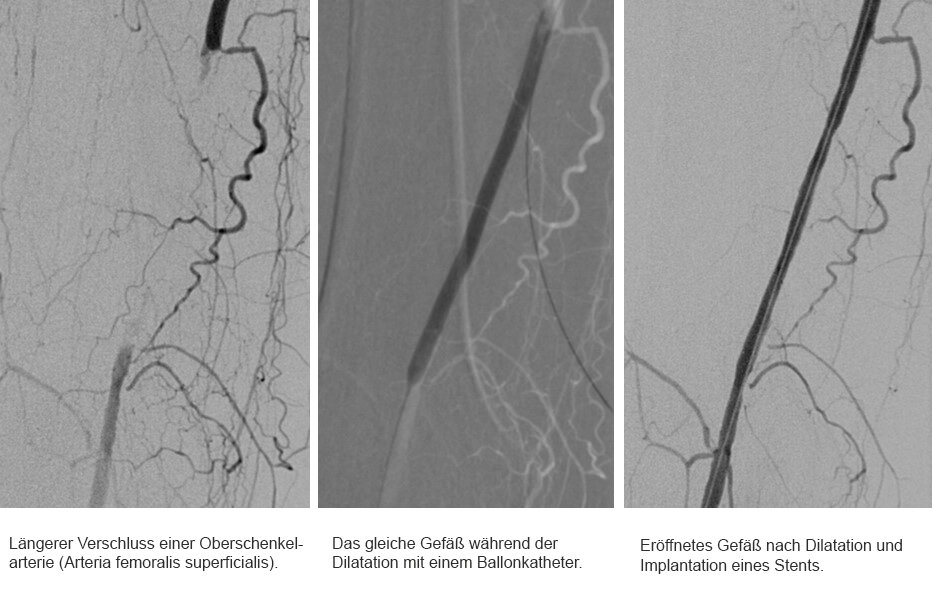

Entscheidet sich der Patient letztendlich für den minimal-invasiven Gefäßeingriff, führen Dr. Merget und seine Kollegen der Radiologie die sogenannte Angioplastie durch. Nachdem die Problemstelle dargestellt wurde, führen sie über die Leistenarterie einen Draht in das betroffene Gefäß ein. Um den Verschluss überwinden zu können, erstellen sie eine „Roadmap“ des Problembereichs. Haben sie die Problemstelle mit dem Draht passiert und sind sie wieder im plaquefreien Teil des Gefäßes angelangt, wird ein Ballonkatheter hinterhergeschoben. Der Ballon wird an der Problemstelle platziert und aufgepumpt (dilatieren). Dabei kommt je nach Gefäß und Katheter ein Druck von bis zu 18 bar zum Einsatz. Zum Vergleich: Einen Autoreifen befüllt man in der Regel mit 2,0 bis 2,5 bar. „Normalerweise halten wir den Druck circa zwei Minuten lang aufrecht. Danach lassen wir den Druck ab und schauen uns das Gefäß an. Ist der Gefäßdurchschnitt ausreichend weit und die Gefäßwand glatt, dann waren wir bereits erfolgreich. Die Plaques wurden an der Wand festgedrückt. Ist das Gefäß dagegen noch verengt oder bestehen Verletzungen der Gefäßwand (Dissektionen), die den Blutstrom noch begrenzen, wird die Prozedur meistens noch einmal wiederholt, ggf. über einen längeren Zeitraum als zuvor“, erklärt Dr. Merget das Vorgehen. Ist auch nach wiederholtem Dilatieren kein zufriedenstellendes Ergebnis erzielt worden, kann ein Stent - ein Gitterröhrchen zur langfristigen Wandstabilisierung - eingesetzt werden. Je nach Gefäßregion kann es auch sinnvoll sein, gleich einen Stent zu implantieren. In sehr beweglichen Körperregionen, wie z. B. dem Kniegelenk, versucht man dagegen, soweit wie möglich auf einen Stent zu verzichten. Schließlich ist das Risiko, dass er dort bricht, leicht erhöht.